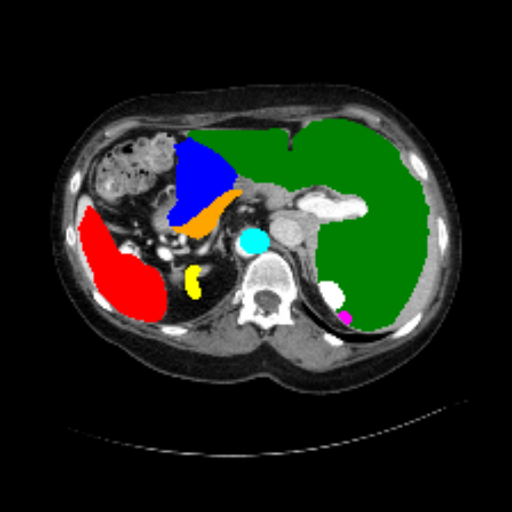

Figure 3 presents a qualitative comparison of segmentation performance on examples from the Synapse, BTCV, ACDC, and ISIC17 datasets. The first two examples (from Synapse) highlight variations in segmentation performance among U-Net, TransUnet, Mamba-Unet, and Swin-Unet. While Swin-Unet performs well in the first example, its performance decreases in the second example, particularly in segmenting the organ highlighted in blue. Additionally, it misclassifies background regions as the class highlighted in orange. In contrast, our approach demonstrates high robustness in segmenting all classes accurately and aligning well with the ground truth masks.

Across BTCV, ACDC, and ISIC17, the comparison methods exhibit varying performance depending on the task and class. For instance, Mamba-Unet struggles to segment multiple organs in BTCV, even misclassifying certain classes as others. In the ACDC dataset, both TransUnet and Mamba-Unet perform poorly in segmenting the three classes. In the last column (ISIC17), Swin-Unet oversegments the skin lesion compared to the ground truth. Unlike the comparison models, our approach consistently delivers effective segmentation across different tasks and datasets.

These qualitative findings further reinforce the quantitative results presented in the experimental section, demonstrating the effectiveness of our MambaCAFU model in handling binary and multi-class segmentation across diverse medical imaging modalities and tasks.

Slice GT Unet TransUnet Mamba-Unet Swin-UMamba MambaCAFU-V1

Figure 3: Visual comparison of segmentation examples from Synapse (first two examples), BTCV (3-4 examples), ACDC (5th example) and ISIC17 (last example). Columns: input slice, ground truth, Unet, TransUnet, Mamba-Unet, Swin-UMamba, and MambaCAFU-V1.